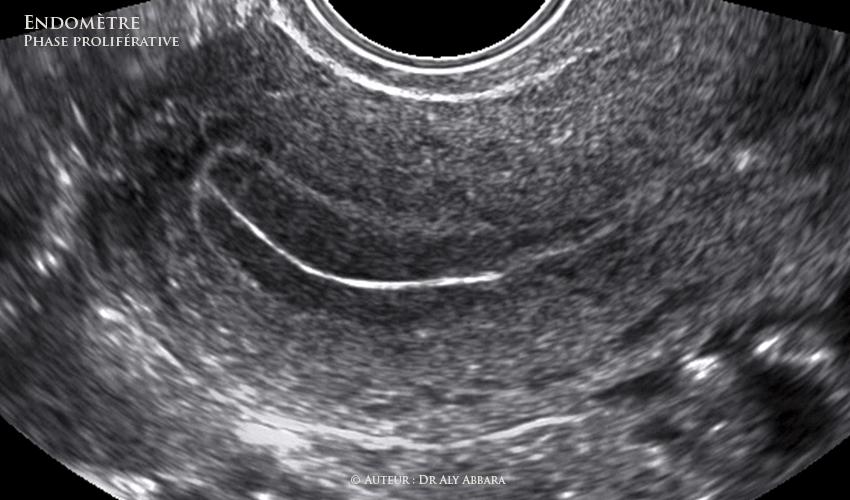

Utérus - la contractilité utérine et l'aspect échographique  de l'endomètre en fin de la phase proliférative (pré-ovulatoire)

Utérus : la contractilité utérine et l'aspect échographique de l'endomètre à la fin de la phase proliférative, avec ovaire gauche contenant un follicule de De Graaf mature (pré-ovulatoire) de 24 mm de grand axe :

Échographie réalisée au 13e jour du cycle menstruel - glaire pré-ovulatoire - endomètre de 11 mm d'épaisseur.

Échographiquement, on observe entre le myomètre et la cavité utérine les couches successives suivantes :

• 1- Un très fin liseré anéchogène (discontinu sur l'image) correspondant à la zone de jonction entre le myomètre et la couche basale de l'endomètre.

• 2- La couche profonde de l'endomètre correspondant à la zone de renforcement basale (plus échogène que le reste de l'endomètre).

• 3- Les couches moyenne et superficielle de l'endomètre qui paraissent hypoéchogènes comparées à la couche basale profonde.

• 4- La ligne de la vacuité utérine qui prend l'aspect d'un liseré axial hyper-échogène.

• Les trois dernières éléments donnent à l'endomètre de la phase proliférative son aspect échographique en trois feuillets.

• La contractilité utérine ondulatoire observée sur cette séquence vidéo peut être expliquée par l'élévation du taux de l'œstrogène et son action sur le myomètre. Ces mouvements ondulatoires de l'endomètre favorisent l'ascension des spermatozoïdes dans la cavité utérine en transformant l'endomètre en tapis roulant (explication personnelle).